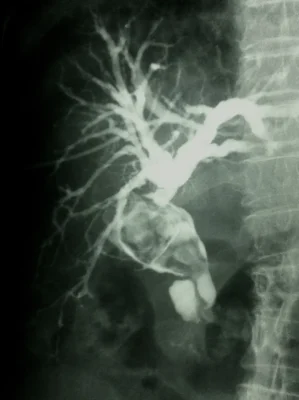

Colangioresonancia: este estudio permite evaluar la presencia de Cálculos en las vías biliares, esta condición corresponde a una enfermedad más compleja y requiere el drenaje de cálculos de la vía biliar adicionalmente a la Colecistectomía.